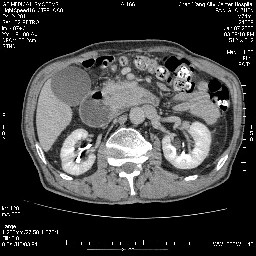

女,74岁,呕吐10余日

壶腹部的占位性病变,考虑为十二指肠癌并梗阻,但脾内多发性低密度区为转移吗?

还有胃、脾之间可见有侧支循环建立。左肾盂积水。

考虑来源于十二指肠水平段的恶性占位,侵及周围组织,特别是胰腺,可见区域淋巴结肿大,左侧下腔静脉畸形。

双肾多发小囊肿;左肾积水。

十二指肠水平段腔内占位伴梗阻,中等度较为均匀的强化,洗脱慢,区域淋巴结显示增多,符合腺癌表现。下腔静脉变异。

十二指肠降段扩张,水平段狭窄成鼠尾状,肠壁明显增厚,胰腺勾突增大成不均匀强化,其内可见低密度区,胆囊增大,1十二指肠水平段腺癌侵犯胰腺勾突可能大,2胰腺癌侵犯十二指肠(只有胆囊增大没有肝内外胆管扩张不好解释)代除外.

十二指肠降段扩张,水平段狭窄成鼠尾状,肠壁明显增厚,胰腺勾突增大成不均匀强化,其内可见低密度区,胆囊增大,1十二指肠水平段腺癌侵犯胰腺勾突可能大,2胰腺癌侵犯十二指肠 。

今日手术结果:胰腺钩突癌侵犯十二直肠,腹腔淋巴结转移.